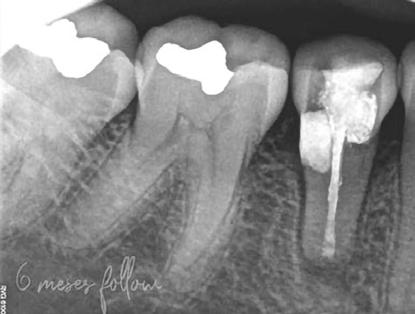

1. ábra: A 15-ös foggyökér meziális felszíne mellett látható radiolucens elváltozás, illetve a felvételen látható a korábban behelyezett gyökértömés, a parapulpális csap segítségével elhorgonyzott csonkfelépítés és a fogat borító cirkonkorona. –2. ábra: A saggitalis irányú CBCT-metszeten jól megfigyelhető az állcsontgerincet elérő radiolucens elváltozás. – 3. ábra: Az axiális irányú CBCT-metszeten egyértelműen látható a kezeletlen palatinális gyökércsatorna, valamint a radiolucens elváltozás mezio-disztális kiterjedése is jól megítélhető. – 4. ábra: A palatinális gyökércsatorna szelektív endodonciai kezelése során először gyógyszeres zárás került behelyezésre. – 5. ábra: A gyógyszeres zárás során alkalmazott kalcium-hidroxid alapú paszta a szulkuszon keresztül a szájüregbe extrudálódott. – 6. ábra: A gyökértömő anyag a középső és apikális gyökéri harmad határán lévő laterális csatornán keresztül a periapikális térbe extrudálódott. 7. ábra: A kezelések befejezését követően 4 évvel készült röntgenfelvételen jól látható a csontállomány gyógyulása és a fiziológiás gyökérhártyarés újbóli kialakulása. –8. ábra: A peroperatív CBCT-felvétel alapján készített koronális irányú metszeten jól látható a gyökércsúcs körül lévő periapikális felritkulás. – 9. ábra: A kezelések befejezése után 4 évvel készített CBCT-felvételen a gyulladásos lézió teljes megszűnése észlelhető.

Először kalcium-hidroxid alapú ideglenes gyógyszeres zárás került a palatinális csatornába (UltraCal XS, Ultradent Products; 4–5. ábra), amelyet 6 hét után a végleges gyökértömés elkészítése előtt eltávolítottunk. A gyökértömés elkészítése során meleg vertikális kondenzációs technikát alkalmaztunk. Radiológiai felvételen megfigyelhető volt, hogy a gyökértömő anyag egy laterális csatornán keresztül kis mennyiségben a periapicalis térbe extrudálódott (6. ábra). A 4 évvel később készített kontrollfelvételeken a lézió gyógyulása volt megfigyelhető (7–9. ábra). A vizsgálati eredmények és a kezelés kimenetele egyértelműen igazolta, hogy nem gyökérfraktúrával álltunk szemben, tehát a kezdeti diagnózis tévesnek bizonyult. Ez is azt erősíti, hogy korlátozott mennyiségben rendelkezésre álló adatok alapján nem lehet pontos diagnózist felállítani. Manapság szinte elengedhetetlen a CBCT-felvételek endodonciai beavatkozások során történő használata, feltéve, ha ezek elkészítése során az ALARA elv (as low as reasonably achievable) betartásra kerül.